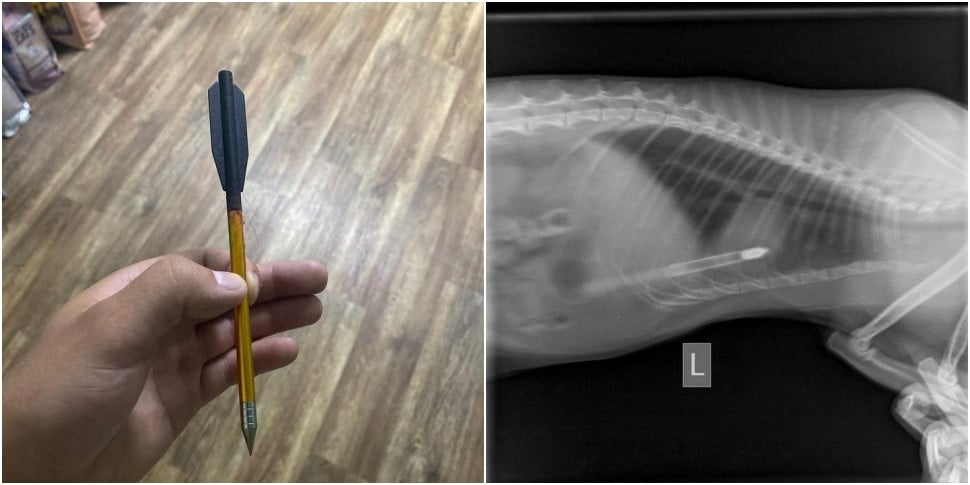

— Ребята приезжают, я осматриваю котика — и что вы думаете? В котике торчит стрела от арбалета — 17 сантиметров, — которая прошла ему через два легких, — говорит на видео врач.

Сообщается, что кот идет на поправку, а милиция ищет живодера.